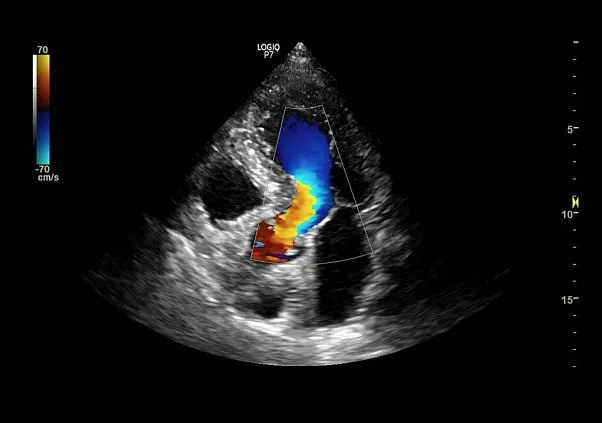

Клинические изображения

Благодаря технологии XDClear клинические изображения становятся более чёткими, с минимальным уровнем шумов и артефактов. Интеллектуальные алгоритмы обработки данных, поддержка мультичастотных датчиков и автоматические функции — такие как допплерография, 3D/4D-визуализация и автоматические измерения — позволяют проводить широкий спектр исследований с высокой точностью. Удобная панель управления, регулируемый монитор и компактные размеры делают использование аппарата максимально комфортным.

- Инновационные инструменты, в том числе недопплеровская визуализация кровотока в B-режиме (B-Flow), 3D/4D сканирование, эластография, стресс-эхокардиография, тканевая допплерография (TVI/TVD) и УЗИ с контрастным усилением (CEUS).